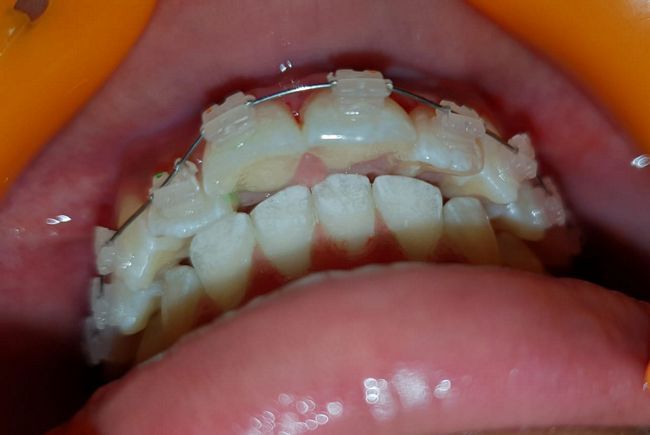

Intra-oral : Mid-treatment : Frontal, Right & Left Lateral View